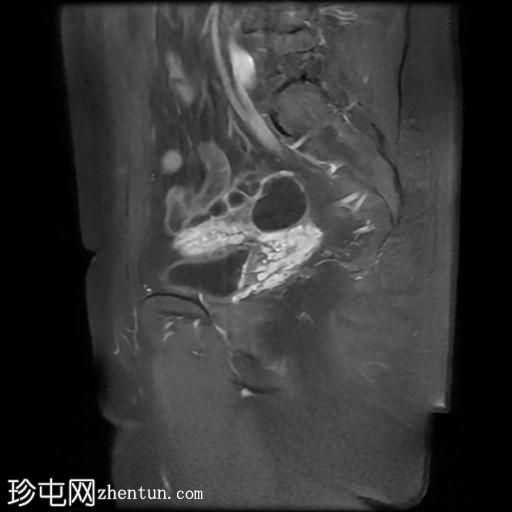

矢状位

T2加权像

右侧输卵管呈管状囊性扩张,直径达30 mm,提示输卵管积水,呈均匀液体信号,无实性成分。

左侧输卵管亦有轻度扩张,直径26 mm,符合输卵管积水表现。

右侧卵巢可见一单纯性卵巢囊肿,大小约35 x 40 mm,呈正常液体等效信号。

宫内节育器位置正常。

MRI 检查结果显示双侧输卵管积水和右侧卵巢单纯性囊肿。总体而言,所有附件和盆腔检查结果均显示良性 MRI 特征(O-RADS 2 类),无恶性肿瘤迹象。